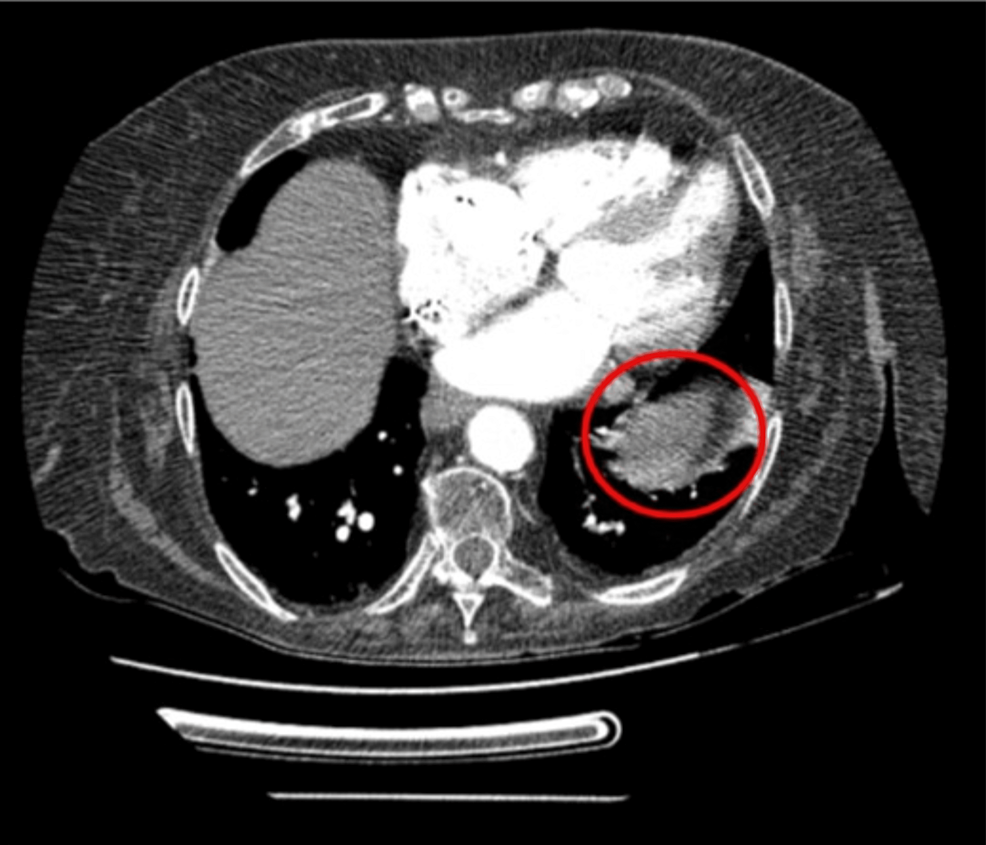

Adenocarcinoma is a tragically common iteration of lung cancer. Risk factors included primary or secondary exposure to tobacco smoke, family history of the disease, and occupationally related hazards, among others. Metastasis to various distant organs may pre…